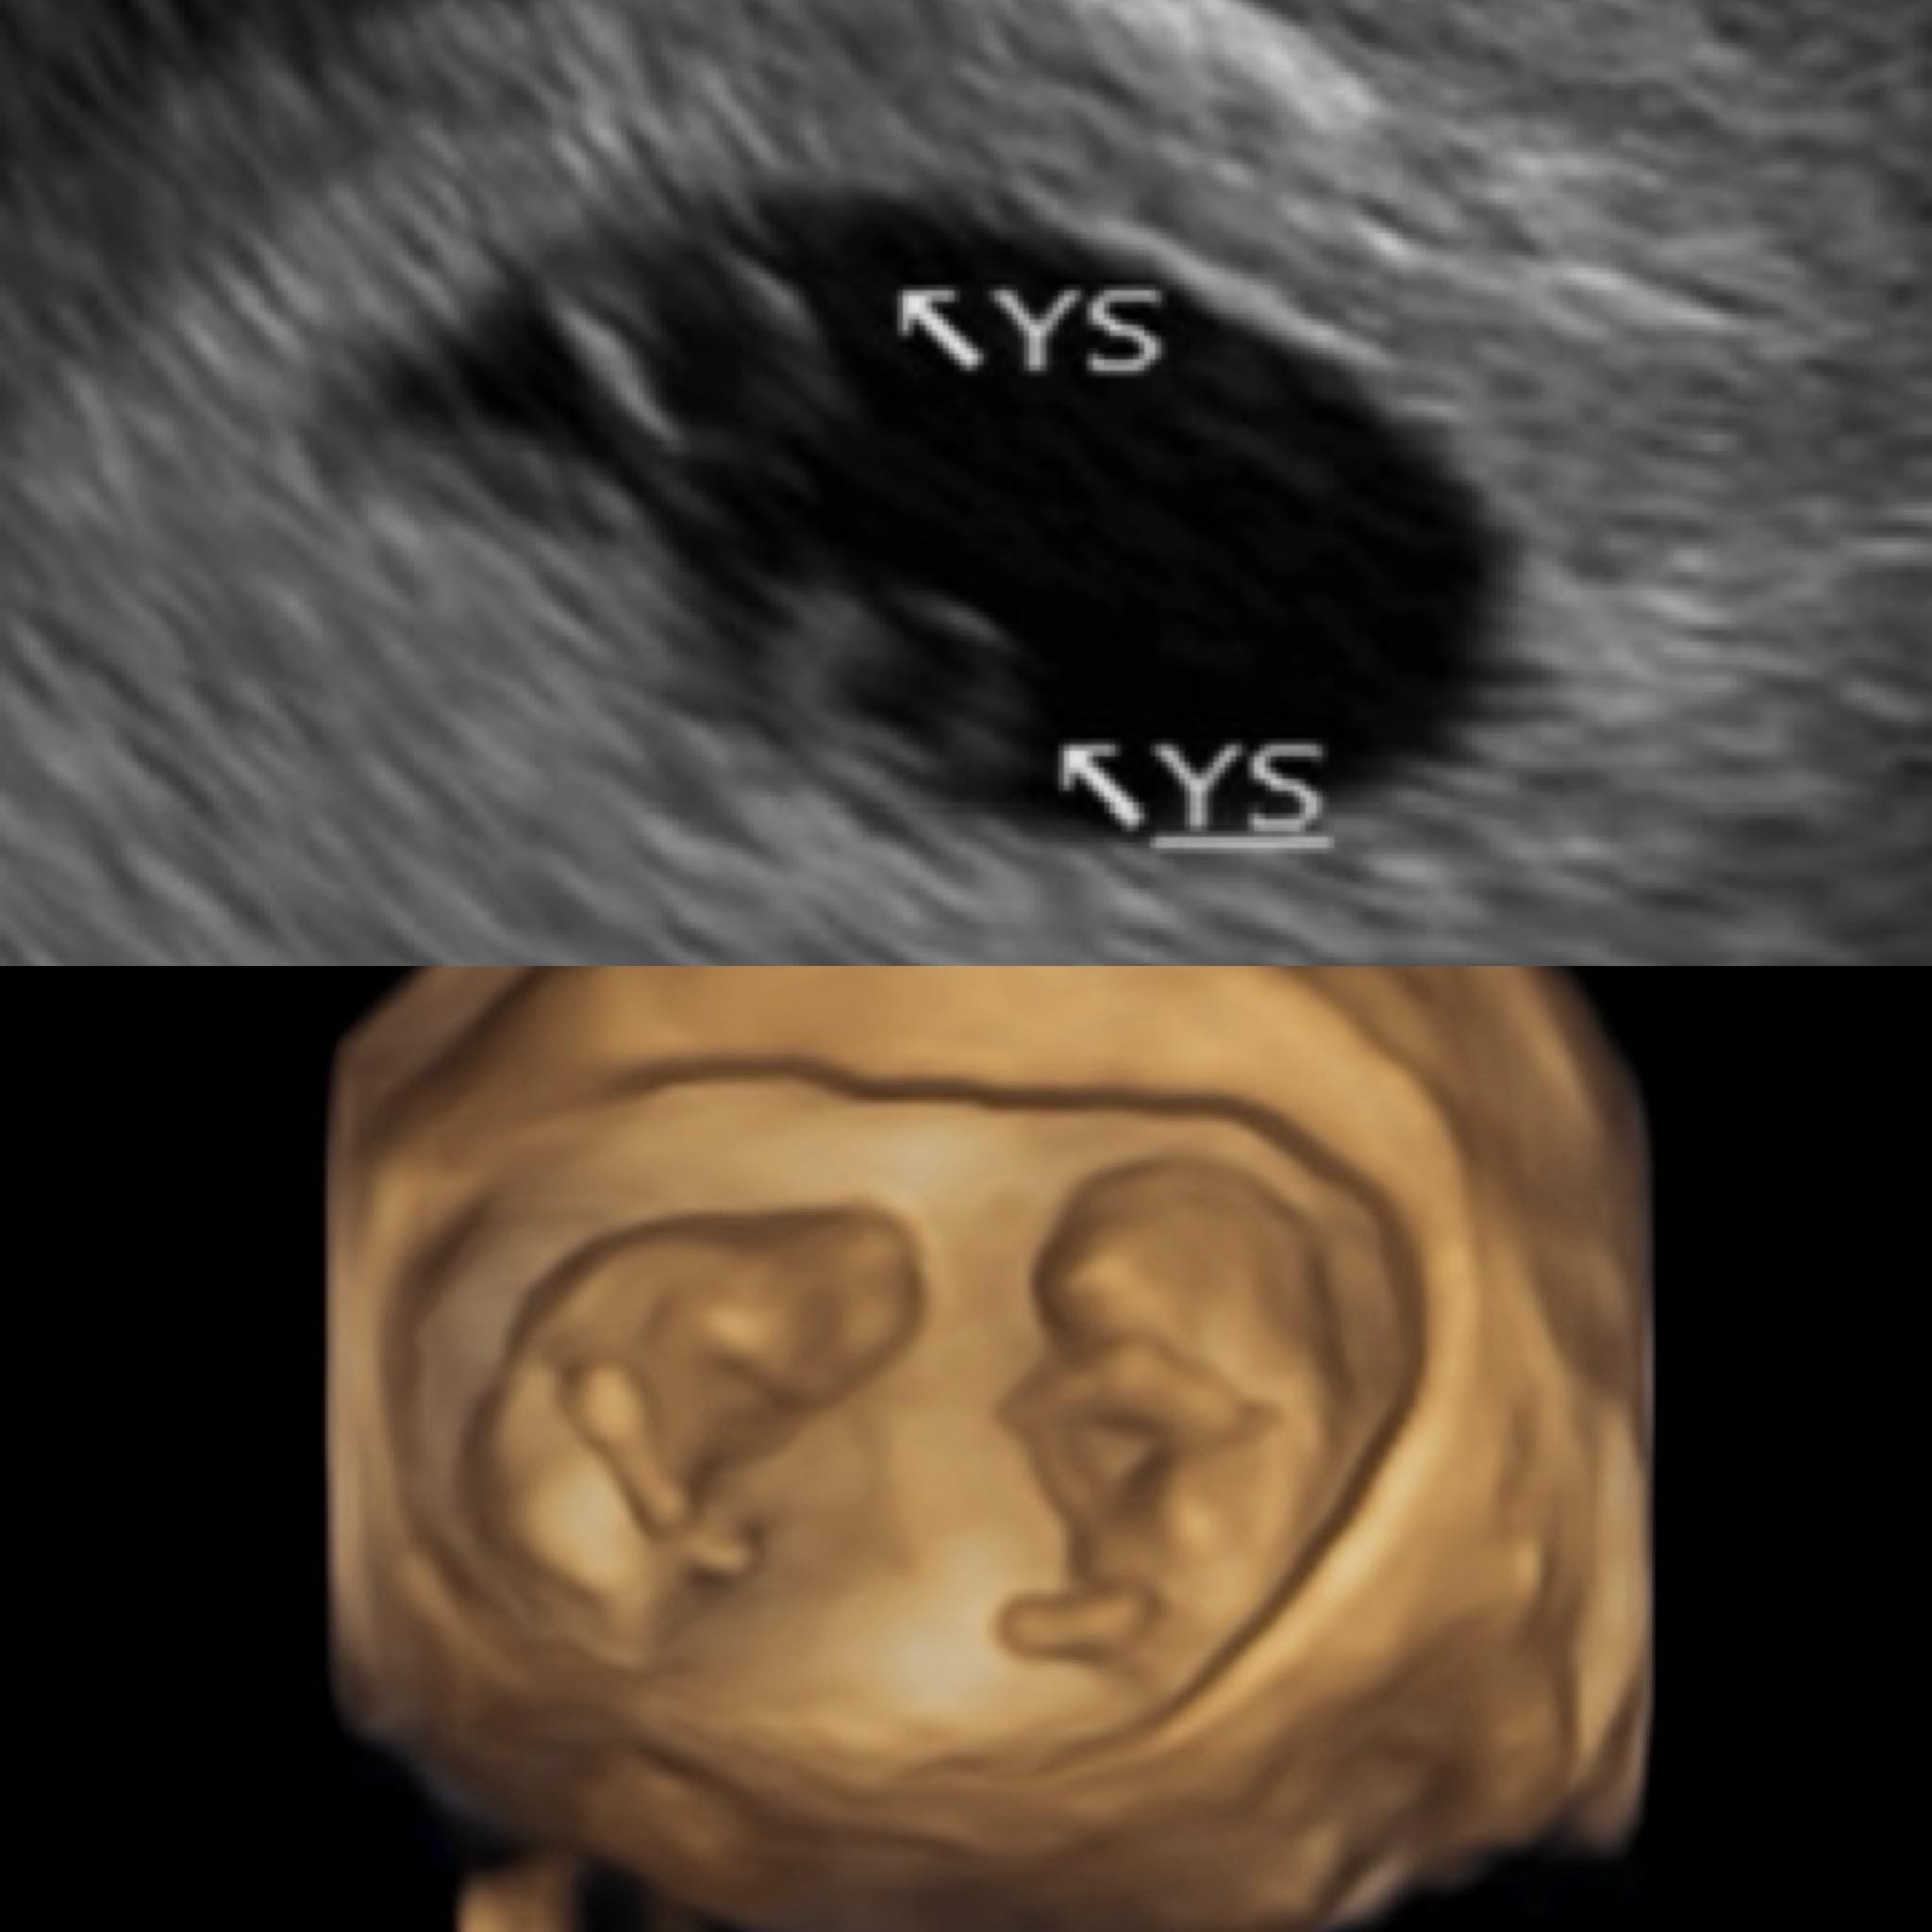

鄭家純今天在臉書發文報喜,目前已經懷孕12週,是同卵雙胞胎,回憶曾跟無緣的小孩介紹阿寶,像媒人一樣把人格特質、身家調查都說得很詳細,推薦寶寶回來,意外地還多揪了手足一起來。

經過2次產檢,得知是雙胞胎,鄭家純坦言當時才第5週,驚喜只持續一下,因為同卵雙胞胎比異卵的風險高,還有分單羊膜還是雙羊膜,但寶寶們很貼心,讓她在6週聽到心跳,瞬間眼淚掉下來,因為上次沒有聽到。到了第8週,確認是雙羊膜,安心很多,不用再查資料看到失眠。

鄭家純目前已懷孕12週。(圖/翻攝自鄭家純臉書)